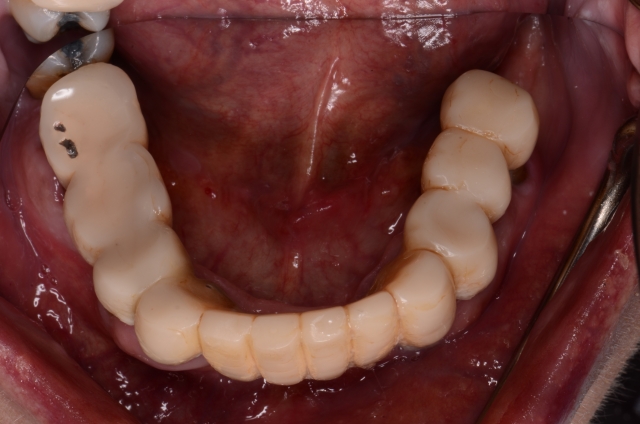

Photography is the linchpin of the entire co-discovery process. We take six pictures in every new case. Spear teaches that these are the six images that will improve case acceptance. Here’s an example:

Rampant root caries, extreme worn dentition and the corrosive effects of GERD are all effectively demonstrated with these photos. These photos get the ball rolling on patients requiring more comprehensive treatments due to a terminal dentition.